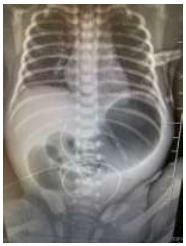

Foi solicitada avaliação de um recém-nascido à termo, com 1 dia de vida, internado em leito de UTI neonatal devido a vômitos biliosos após todas as mamadas. O neonatologista refere que mãe não realizou o pré-natal adequado. Exame físico: distensão de andar superior de abdome, indolor à palpação. Radiografia de abdome: imagem a seguir.

Assinale a alternativa que apresenta o diagnóstico mais provável: